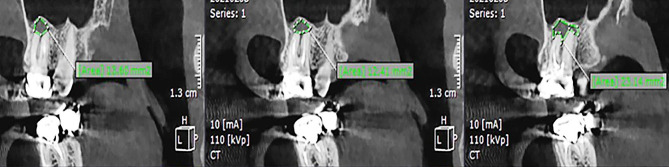

Data on the four dependent variables were recorded: presence of PL, PL volume, presence of CBD, and BPBH. PL was identified as absent when intact periapical bone structures could be detected (diameter of the periapical radiolucency under 0.5 mm), and otherwise as present [ref. 25]. In order to evaluate PL volume, the tooth was viewed in the sagittal plane with one-millimeter interslice intervals. The surface area of the PL in each slice was measured using the area tool in the software (Fig. 2). Considering the PL as an asymmetrical 3D object, its volume was measured using the formula presented below, where h represents the interslice interval, and S denotes the surface area of partial frustum bases. The accuracy of this measurement method has been proven in several publications [ref. 18, ref. 26, ref. 27].

CBD was observed from the coronal plane slices, showing the buccolingual bone surrounding the roots. BPBH was defined using the ruler tool to measure the apicocoronal height of the bone covering the roots.